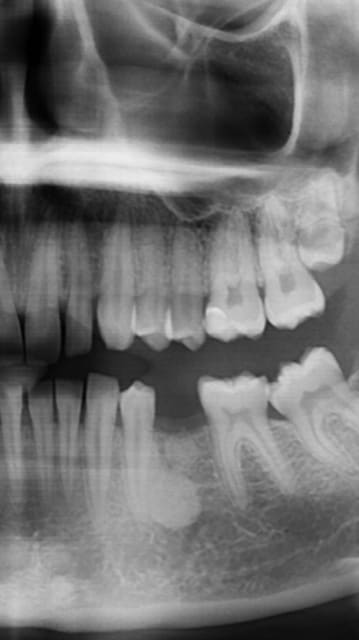

J'ai un cas d'une jeune vingtaine agénésie 35 qui consulte pour pose implant dont apex serait en contact cémentôme

Est ce que quelqu'un a déjà eu le cas et pose implant en contact cémentôme?

Contre indication? quel risque ?

Je me demande juste qu'il est la qualité de l'interface implant cémentôme

Cémentointégration si on peut appeler cela ainsi ou ankylose comme pour les implants zircone